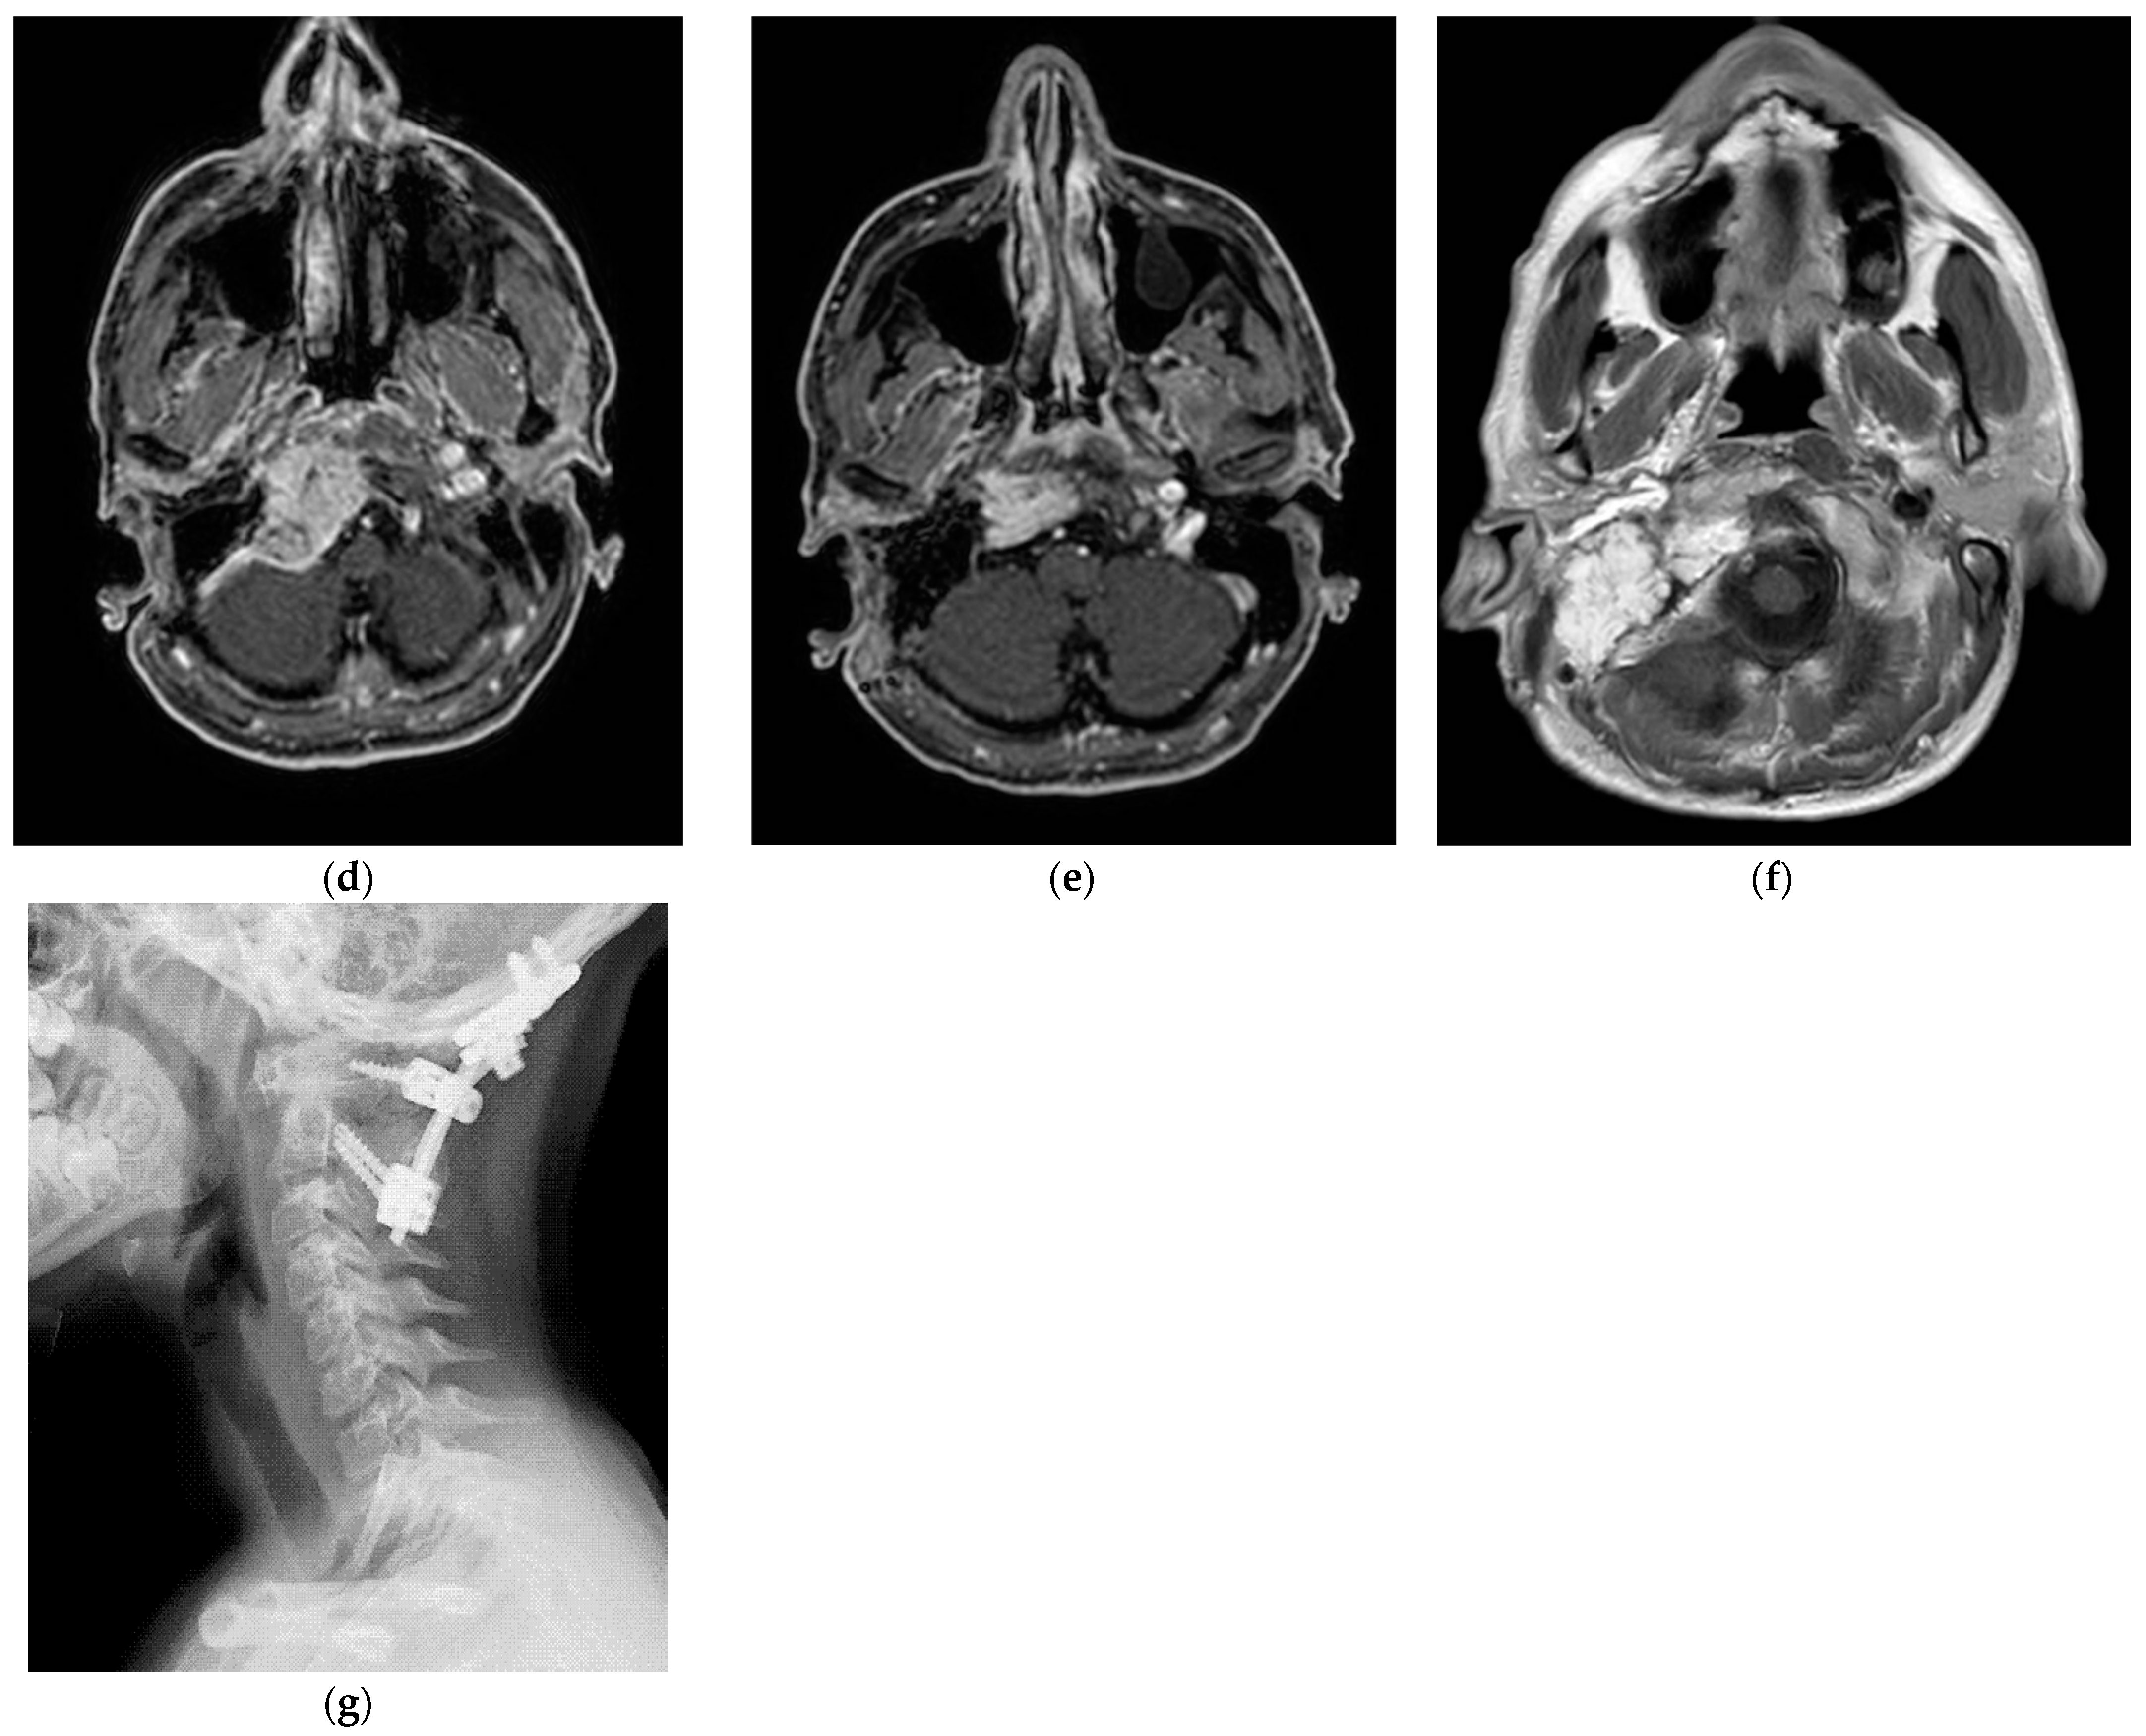

5.1. Case 1: (C4Di2)

5.6. Case 6: (C4Di2Vi)